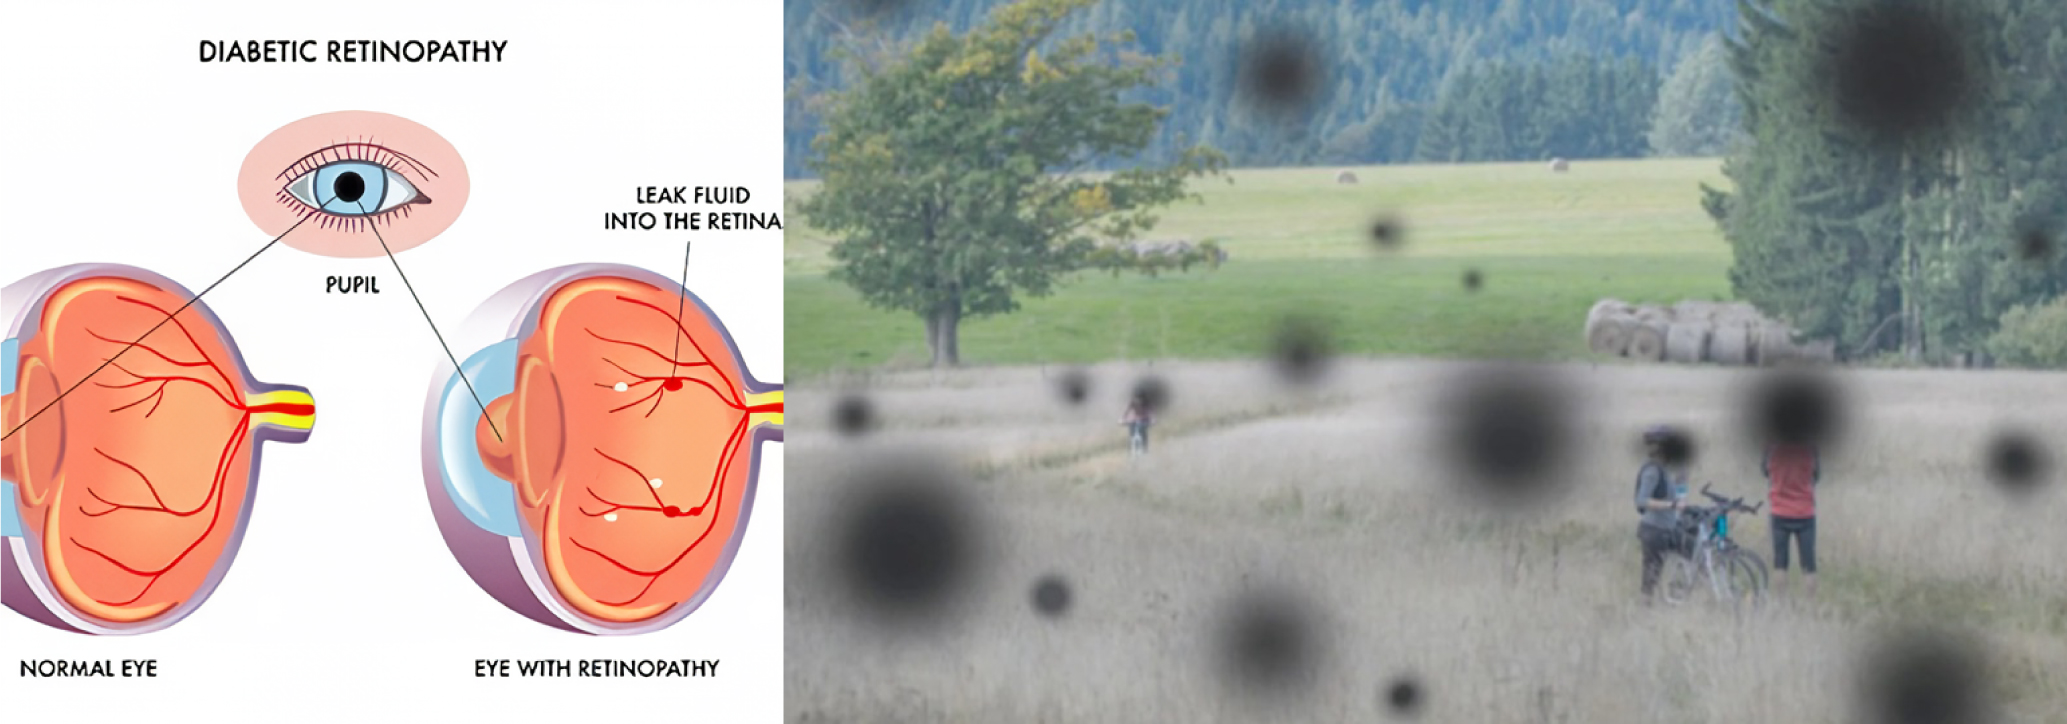

糖尿病视网膜病变 (DR)

糖尿病性视网膜病变 (DR) 是糖尿病最常见的并发症之一,随着病程延长,发病率显著增加,长期糖尿病患者几乎普遍患病,是全球重要的致盲原因。该病分为非增殖性和增殖性两种类型:非增殖性DR表现为眼底微血管瘤、出血、渗出等,而增殖性DR则出现新生血管、玻璃体出血和视网膜脱离等严重并发症。早期发现和管理糖尿病视网膜病变对于预防糖尿病患者失明至关重要。

中医将糖尿病归为“消渴病”,认为DR是“消渴目病”,病因与阴虚、饮食失调、情绪波动和过度劳累有关。气阴两虚和血瘀是贯穿病程的主要证候。中医调理强调个体化调整,并建议在必要时结合西医的激光光凝和抗VEGF眼内注射等方法,以最大限度地保护患者的视力。